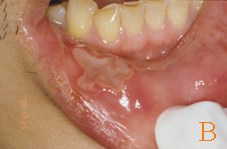

在台灣的發生率約10.5%,臨床上復發性口腔潰瘍有三種型態,小型、大型、泡疹型(如:圖一)。小型的復發性口腔潰瘍為1公分以下,潰瘍約7至14天會復原,小型的復發性口腔潰瘍雖然很小,但有時相當的疼痛。大型的復發性口腔潰瘍直徑約1-3公分,通常要2-6個星期才會癒合,且可能會結痂,大型的復發性口腔潰瘍好發於唇黏膜、軟?等處。泡疹型復發性口腔潰瘍,數目很多,集結成團,且常復發,每個潰瘍直徑約1-3 mm,有時多個小潰瘍會集結起來成為大潰瘍,泡疹型復發性口腔潰瘍約7-10天會痊癒,通常從成人期開始發生,且好發於女性患者。

圖一: 復發性口腔潰瘍。(A)發生於舌尖黏膜之小型復發性口腔潰瘍病變。(B)發生於右下唇黏膜之大型復發性口腔潰瘍病變。(C)發生於上唇黏膜之泡疹型復發性口腔潰瘍病變。